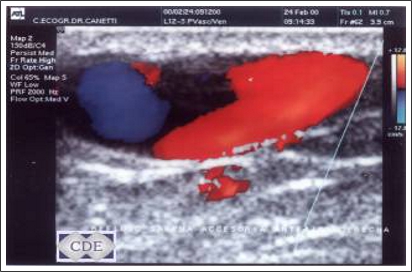

Eco Doppler. Vascular y arterial

Es un estudio que permite diagnosticar alteraciones venosas (várices), arteriales (trombosis) de miembros inferiores, superiores y de los vasos del cuello. Es totalmente incruento pues es superficial, no necesita ninguna preparación y presenta una efectividad diagnostica altamente satisfactoria. Lo efectuamos en nuestro Centro diariamente.